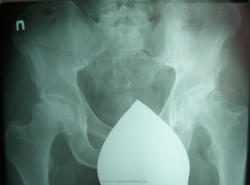

Пол пациента: Мужской пол Тип патологии: Врожденная патология Область исследования: Скелетно-мышечная система Методы исследования: Rg Мужчина 40 лет после падения с 3 этажа почувствовал болезненность в т\б суставах. Травма произошла около3 месяцев назад. Был сделан снимок. https://radiomed.ru/sites/default/files/styles/case_slider_image/public/user/712/sl273619.jpg?itok=ZJ42angR https://radiomed.ru/sites/default/files/styles/case_slider_image/public/user/712/sl273620.jpg?itok=_YJo-xg7 ID:13714 Wed, 27/04/2011 - 19:45 #1 Игорь Иванович Offline Last seen: 3 years 11 months ago Joined: 23.01.2010 - 14:56 Posts: 3695 Асептический некроз головки бедренной кости, стадию подскажут академики сайта. Thu, 28/04/2011 - 06:48 #2 Kuzmitch Offline Last seen: 12 years 8 months ago Joined: 01.10.2010 - 18:20 Posts: 171 Позволю себе предложить стадию импрессионного перелома переходящую в стадию секвестрации, выраженного артроза нет Thu, 28/04/2011 - 15:16 #3 lupan Offline Last seen: 6 years 11 months ago Joined: 07.01.2010 - 17:17 Posts: 1406 Игорь Иванович wrote: Асептический некроз головки бедренной кости, стадию подскажут академики сайта. Обоих костей. Великое преймущество врача заключается в том, что он не обязан следовать собственным советам. ( А. Кристи)

Асептический некроз головки бедренной кости, стадию подскажут академики сайта.

Обоих костей.